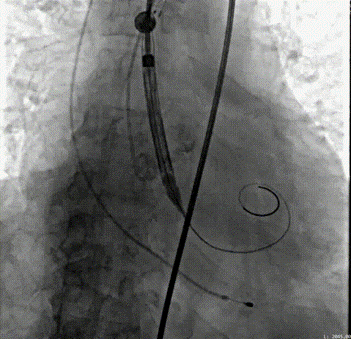

介入瓣置入手术影像。